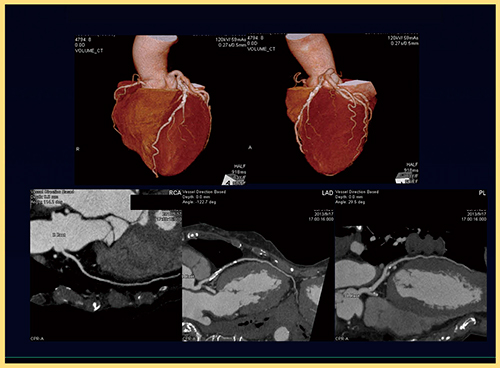

2.超低被ばく冠動脈CTA

面検出器CTは第2世代となったことで,さらなる被ばく低減が可能となり1),低線量(2mSv以下)で撮影した冠動脈CTAでも明瞭な画像を取得できる(図2)。最近では,0.1mSv未満の超低線量冠動脈CTAも報告されており,今後のさらなる低線量化が期待される。

図2 低線量冠動脈CTA(1.39mSv)